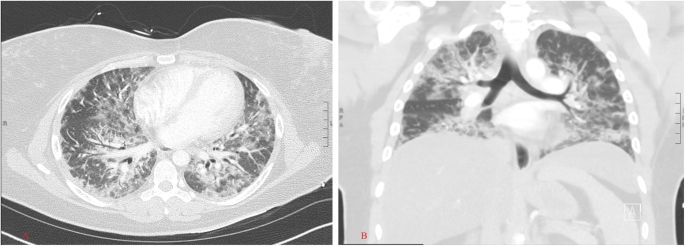

On presentation to the outside hospital, she was febrile, tachycardic, tachypneic, with an oxygen saturation of 85% on nasal cannula at 15 L/min. Respiratory exam was significant for rhonchi bilaterally. Initial labs showed normal white blood cell count, normal creatine, and slightly elevated globulin with normal liver function tests. Her streptococcus pneumonia urinary antigen was positive. She was treated with a course of antibiotics. Computed tomography (CT) scan of the chest revealed no pulmonary embolus and demonstrated bilateral diffuse ground glass patchy opacities throughout the lungs (Fig. 1a-b).

Physical examination revealed diffuse facial hair and hyperpigmented patches at the dorsum of bilateral third metacarpophalangeal joints (Fig. 2). These skin features, along with the lack of muscle weakness and unremarkable muscle enzymes, CT chest findings of bilateral ground glass opacities, double positive MSAs (anti-PL-7 and MDA5), and negative infectious work up, all led to a diagnosis of acute hypoxemic respiratory failure secondary to rapidly progressive interstitial lung disease (RPILD) due to CADM.

The clinical features associated with certain MSA can usually be distinct from one another. Anti PL-7 antibodies are classified under the anti-ARS group. These antibodies are associated with a median age of clinical onset of 60 years old with 90% having non-specific interstitial pneumonia (NSIP) on HRCT and elevated serum creatinine kinase [5]. Anti-MDA5 antibody cases were mostly reported in Japan and rural China; 90% of them have dermatomyositis related skin findings and pulmonary findings of acute ILD with consolidation and ground glass attenuation [5]. Chest CT of MDA5-ILD is reportedly characterized by lower lung consolidation or a random GGO pattern with absence of intralobular reticular opacities and traction bronchiectasis [6]. Anti-MDA5 associated ILD carry a poorer prognosis as compared to anti-ARS associated ILD [7].

In contrast to these previous two cases of anti-ARS antibodies with co-existent anti-MDA5, our patient’s chest CT had extensive ground glass opacities bilaterally without bronchiectasis, which is more indicative of the pulmonary features for anti MDA5 ILD. Interestingly, she was found to have positive testing for both anti-PL7 and anti-MDA5 on repeated MSAs panel testing. Further comparison among these three cases is listed at Table 2.